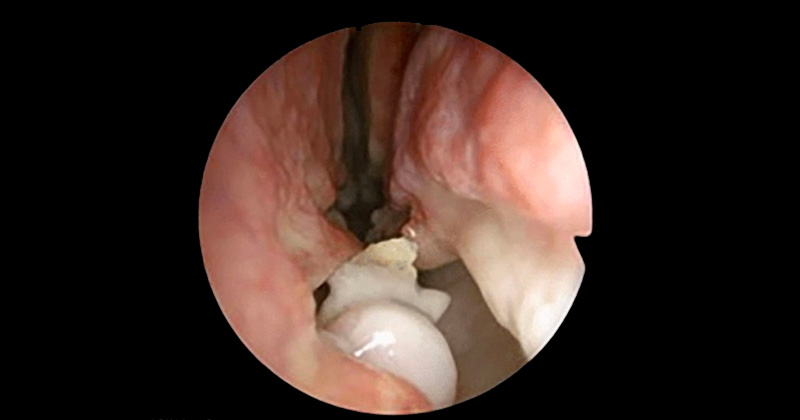

Perdió el olfato, fue al doctor y descubrió un diente creciendo al interior de su nariz

Esta condición sucede es tan rara que solo afecta al 0.1 por ciento de las personas alrededor del mundo.